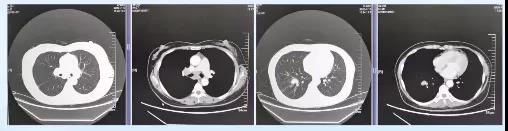

胸部CT:右肺下叶团块并局部支气管阻塞及肺不张,纵隔及右肺门淋巴结肿大,心包少许积液。

2020-07-10胸腹盆增强CT:右肺占位伴局部支气管阻塞及不张,右侧胸膜及斜裂胸膜增厚,心包腔少量积液,纵膈及右肺门淋巴结肿大。

胸腹盆增强CT:右肺占位伴局部支气管阻塞及不张,右侧胸膜及斜裂胸膜增厚,心包腔少量积液,纵膈及右肺门淋巴结肿大